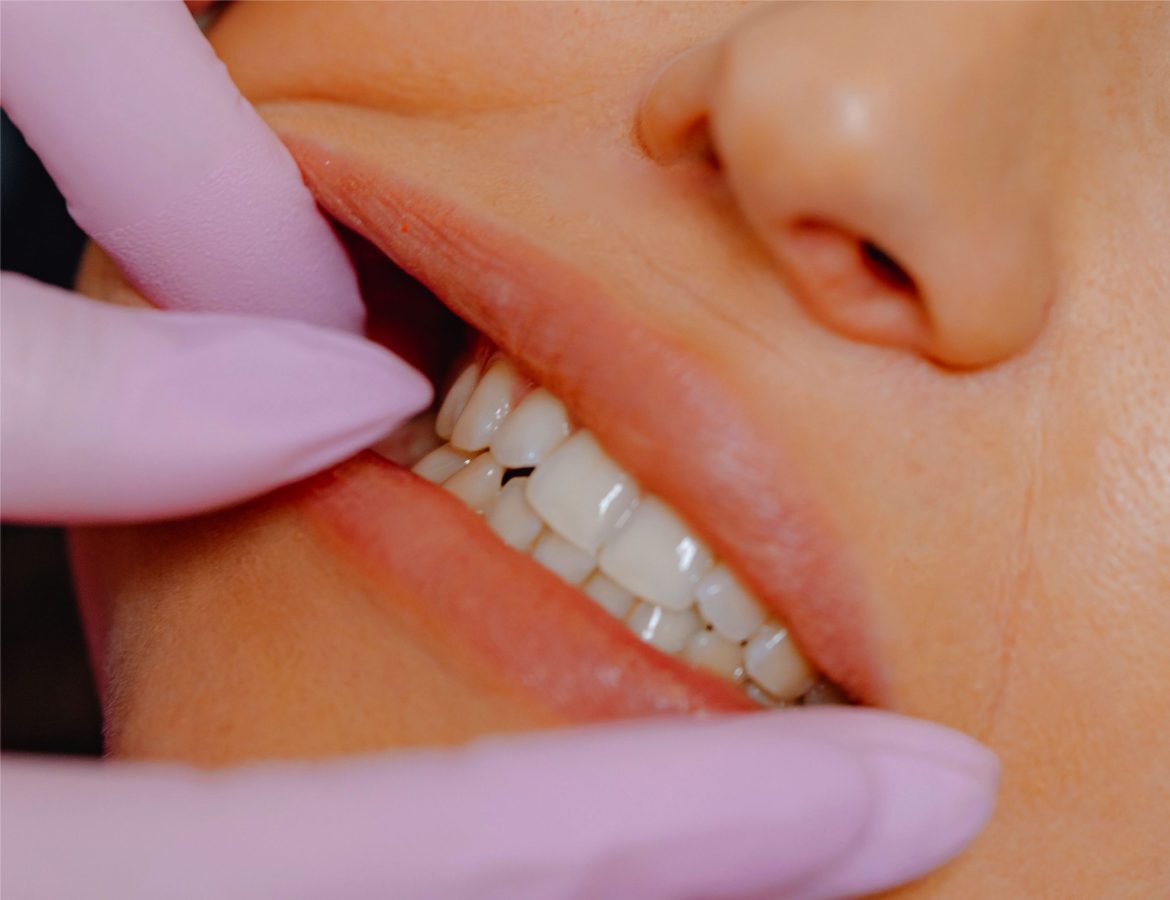

• Natural looking end results

• Precise and accurate implant

• Less Invasive